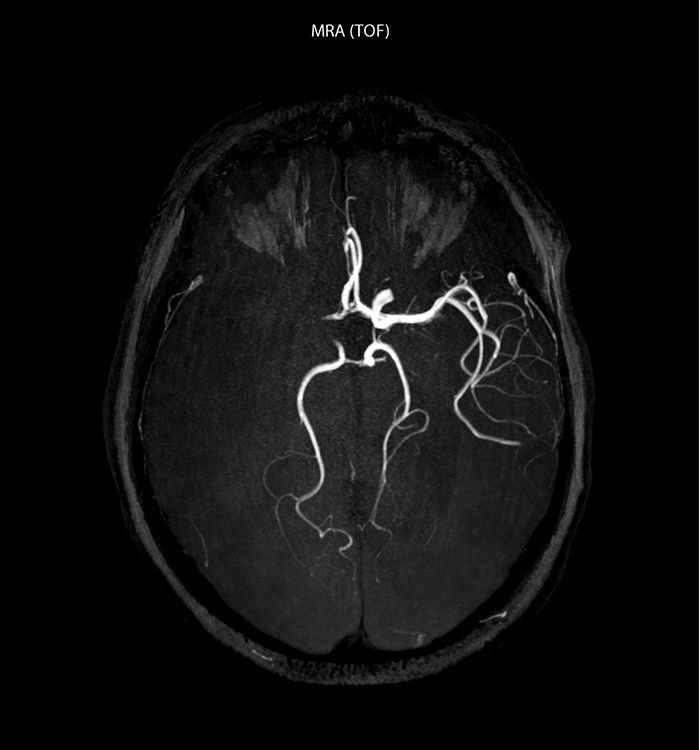

“In France, every stroke is usually imaged with MRI, not CT, even for emergency treatment.” “In France, stroke is usually imaged with MRI, not CT, even for emergency treatment. This is because MRI helps us directly visualize ischemia in the acute phase, but can also help rule out differentials such as MS and hematoma. In addition, we can assess the intracranial and extracranial vessels during the same examination,” says Dr. Savatovsky.

The first challenge in MRI of stroke is speed. The patient typically arrives from an ambulance in the MRI preparation room and the installation is done on a separate dock outside the scanner room. “The venous access is placed during the neurological examination. If the delay from the first symptoms allows the patient to receive thrombolysis we do a very fast examination that typically lasts about 11 minutes including the pre-scans. In the case of transient ischemic stroke we usually add ASL perfusion because in some symptoms with negative diffusion, ASL sometimes indicates a vascular origin.”

“Ingenia provides great flexibility in the parameters setting. We can tune a sequence the way we want,” says Dr. Savatovsky. “For example, in a stroke exam we use a FLAIR sequence of about two minutes instead of the four-minute FLAIR we use for MS. The diffusion is 30 seconds, the T2*-weighted scan is 30 seconds, the angiography scan time is less than one minute. Ingenia is a great scanner in that situation; even with these fast sequences we can achieve good images with good SNR. When the first sequence tells us that it’s not an ischemic stroke but a hemorrhagic stroke, we may switch to a time-resolved angiography to look for vascular malformations and venous thrombosis.

“Every center is different, but for me the ideal protocol for stroke includes diffusion weighted imaging, FLAIR, and fast susceptibility imaging,” says Dr. Savatovsky. “Our fast susceptibility weighted imaging takes 50 seconds, so it’s as fast as T2*-weighted imaging. It visualizes hemorrhage but also the clots. We also do 3D MR angiography that provides information on cervical and brain vessels. If the patient does not need immediate treatment, or if additional information is needed to decide on treatment, we might also add perfusion imaging and post-contrast T1-weighted imaging.”